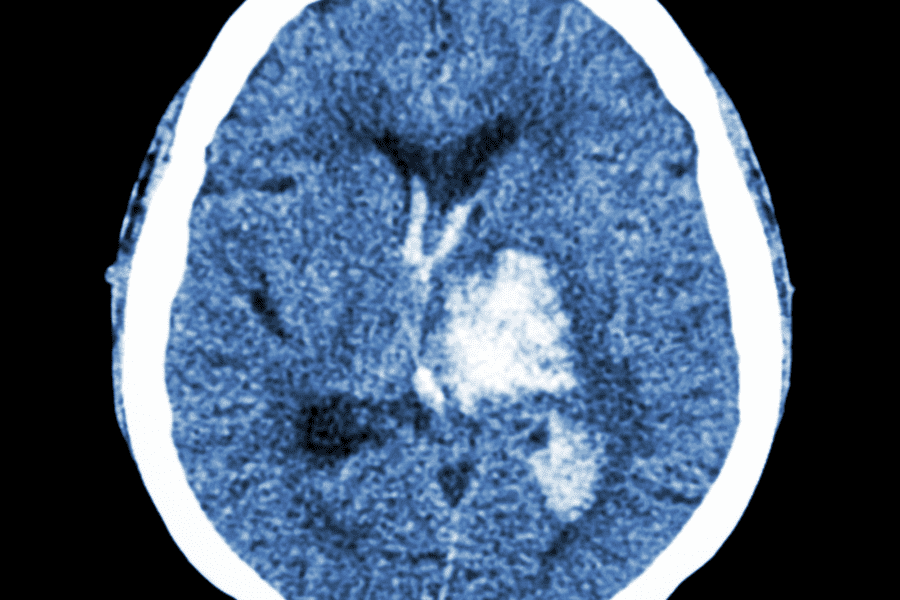

Article originally published in NeuroNews International. The two prevailing techniques used during surgical treatments of traumatic acute subdural haematomas (SDHs)—craniotomy and decompressive craniectomy—have demonstrated broadly similar…